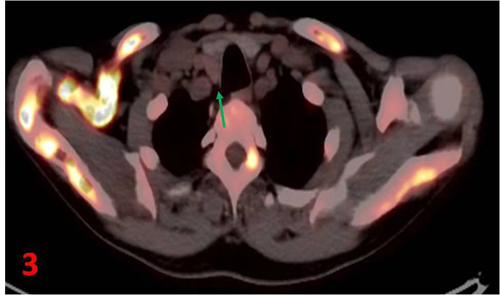

甲狀腺右葉后方見不規(guī)則軟組織密度結(jié)節(jié)(圖3箭),長(zhǎng)徑約2.3cm,未見明顯顯像劑攝取增高區(qū)。

全身多發(fā)骨骼異常,符合甲狀旁腺功能亢進(jìn)性骨病;甲狀腺右葉后方結(jié)節(jié),不除外甲狀旁腺來源病變。雙腎及右側(cè)輸尿管上段結(jié)石,右腎重度積水,左腎輕度積水。